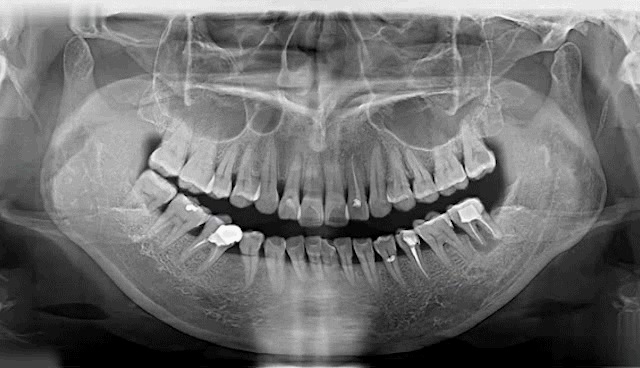

▲Deepcare模拟未来10年口腔变化情况

NO.1 缺牙的危害

牙齿缺失会引起邻牙松动、对牙伸长、引发牙周病,最终牙齿脱落等一系列问题,还会因咬合紊乱致使面容苍老、咀嚼功能变差引发肠胃疾病,甚至影响身体健康。